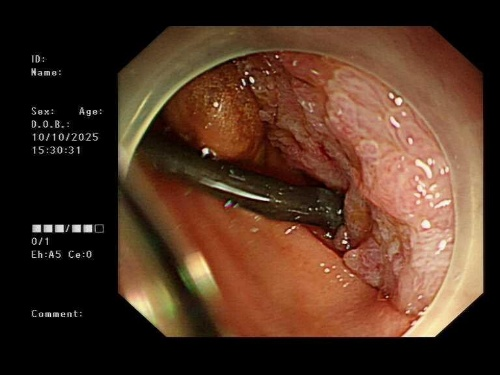

手术室中,一场没有体表切口的“体内造桥工程”悄然开启。

超声内镜探头如同高精度的“GPS导航”,在胃腔内实时扫描,清晰显示出肿瘤的边界、周围血管的搏动,以及最佳“桥墩”定位点。

在超声的实时引导和X光造影的监控下,穿刺、导丝置入、支架释放……

一系列步骤如行云流水。

当那枚双蘑菇头支架在胃与空肠之间成功展开,宛如一朵生命之花在体内绽放,一座避开所有险滩的“人工桥梁”就此贯通。